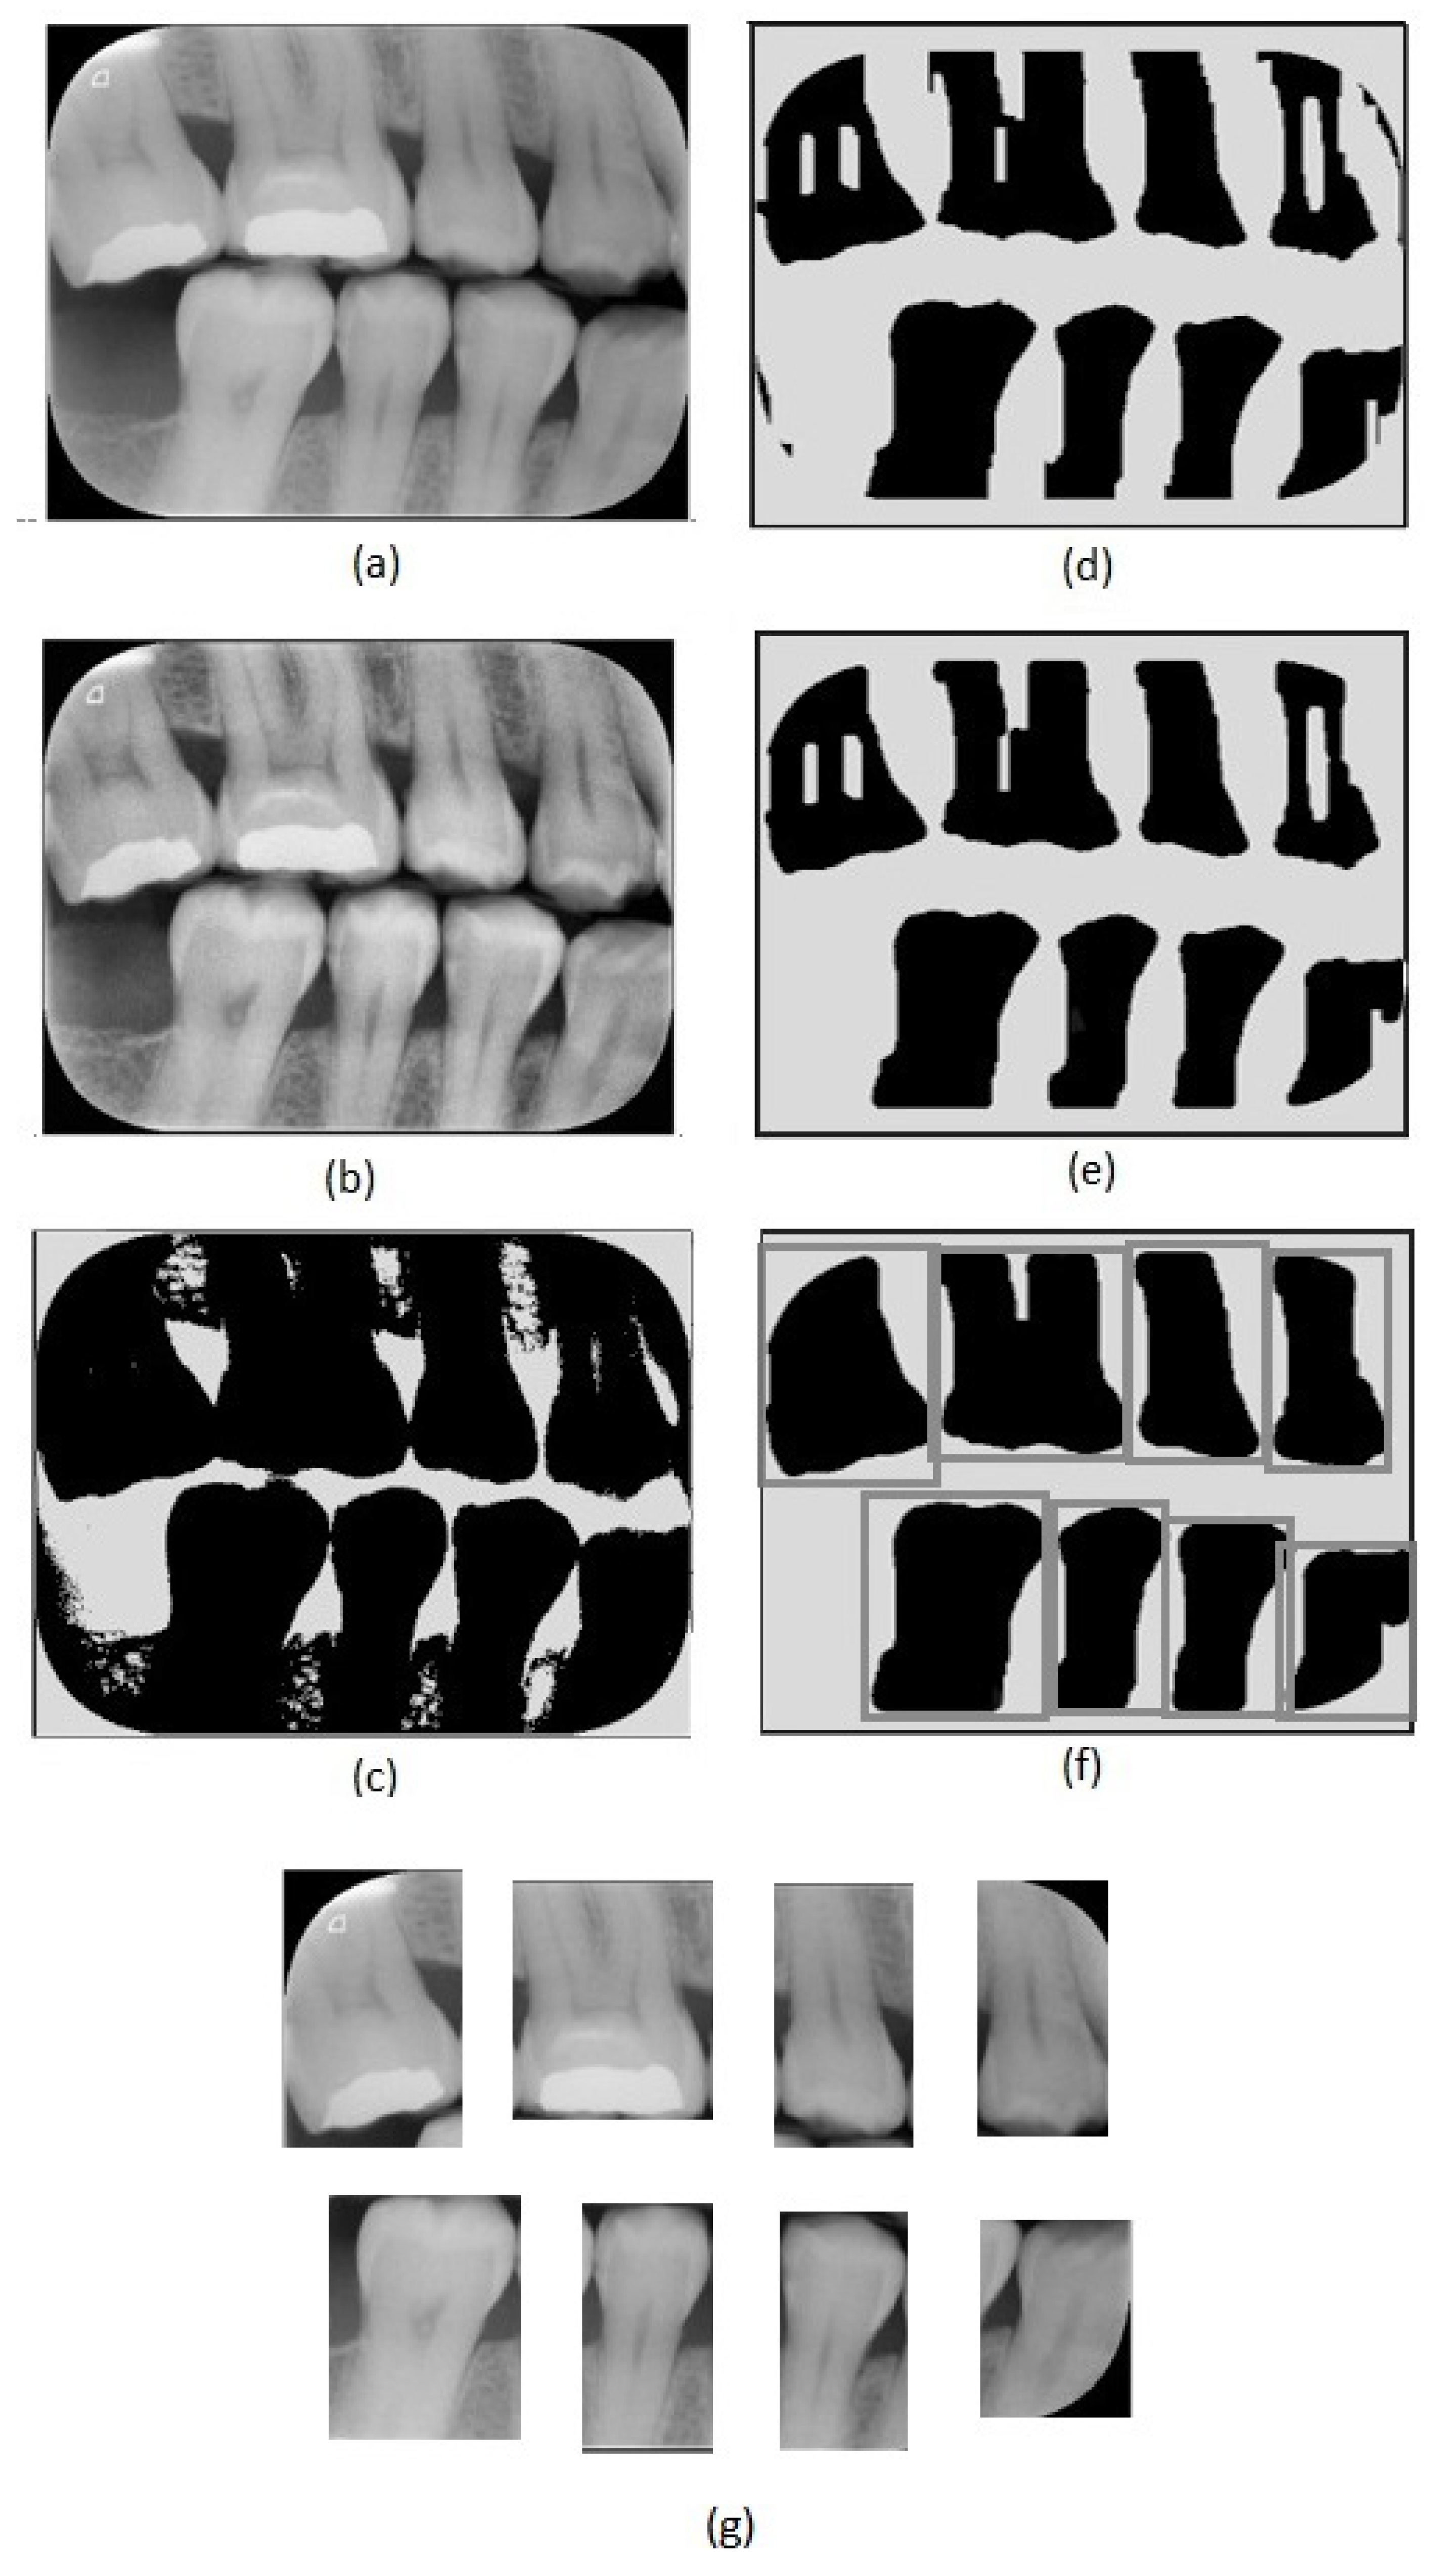

Figure 2.

Image preprocessing steps: (a) original image, (b) adaptive histogram equalization, (c) Otsu’s thresholding, (d) erosion, (e) closing, (f) dilation and tooth region definition, (g) tooth images obtained.

The first step of the proposed method consists of an adaptive equalization operation (Figure 2b), performed to enhance the image’s details, allowing an easier differentiation between background and tooth areas. For this operation, we used the adaptive histogram equalization [21]. This operation considers parts of the image rather than the entire image. It uses the histograms of these parts to calculate local equalizations. Note that in the adaptive equalization, the histograms are created based on a defined neighborhood window. In this work, we tested variations of window sizes and achieved the best visual result using an 8 × 8 window.

In the achieved equalized image, the tonalities of teeth and background areas differ substantially. In this way, binary images can be obtained from the equalized images using a thresholding process. In this work, we used the Otsu thresholding technique [22].

Although the thresholding process properly separates most of the tooth areas from the background areas, some small regions are incorrectly assigned in both areas. This can be easily corrected using morphological operators [23]. Note that, in the binary image resultant from the thresholding (Figure 2c), the tooth areas are of large regions with few flaws. On the other hand, the incorrectly included regions are small and irregular, which can be eliminated easily using morphological operations. Considering the thresholded image (Figure 2c), we first applied an erosion using a structuring element that presents a rectangular shape and size of 130 × 20 (Figure 2d). We chose this specific element for erosion after evaluating the shapes of the incorrectly included regions. On the one hand, smaller elements do not eliminate the undesirable regions entirely; on the other hand, larger elements accidentally remove parts of the identified teeth regions. In our investigation, we also observed that using uniform, symmetrical structural elements, e.g., squares or circles, led to the union of regions of contiguous teeth that were close together. In the opening operation, a circle with a radius of 20 pixels was used as the structural element (Figure 2e). This operation eliminated the remaining undesirable parts. Finally, we applied dilation with a circle with a radius of 15 pixels as a structuring element. This dilation recovered the borders in the tooth areas that were accidentally removed in the erosion operation.

After removing the incorrectly included regions, the binary images are only composed of teeth areas (large and black) in a white background. In the resultant binary image, each area refers to a different tooth. These areas are considered the regions of interest. We created new images covering each tooth defined by the bounding boxes around the regions of interest (Figure 2f). Thus, we repeatedly cropped the original bitewing image, using the limits defined by the bounding boxes to obtain individual images for each tooth (Figure 2g). Data processing was performed using Python and the scikit-image library.